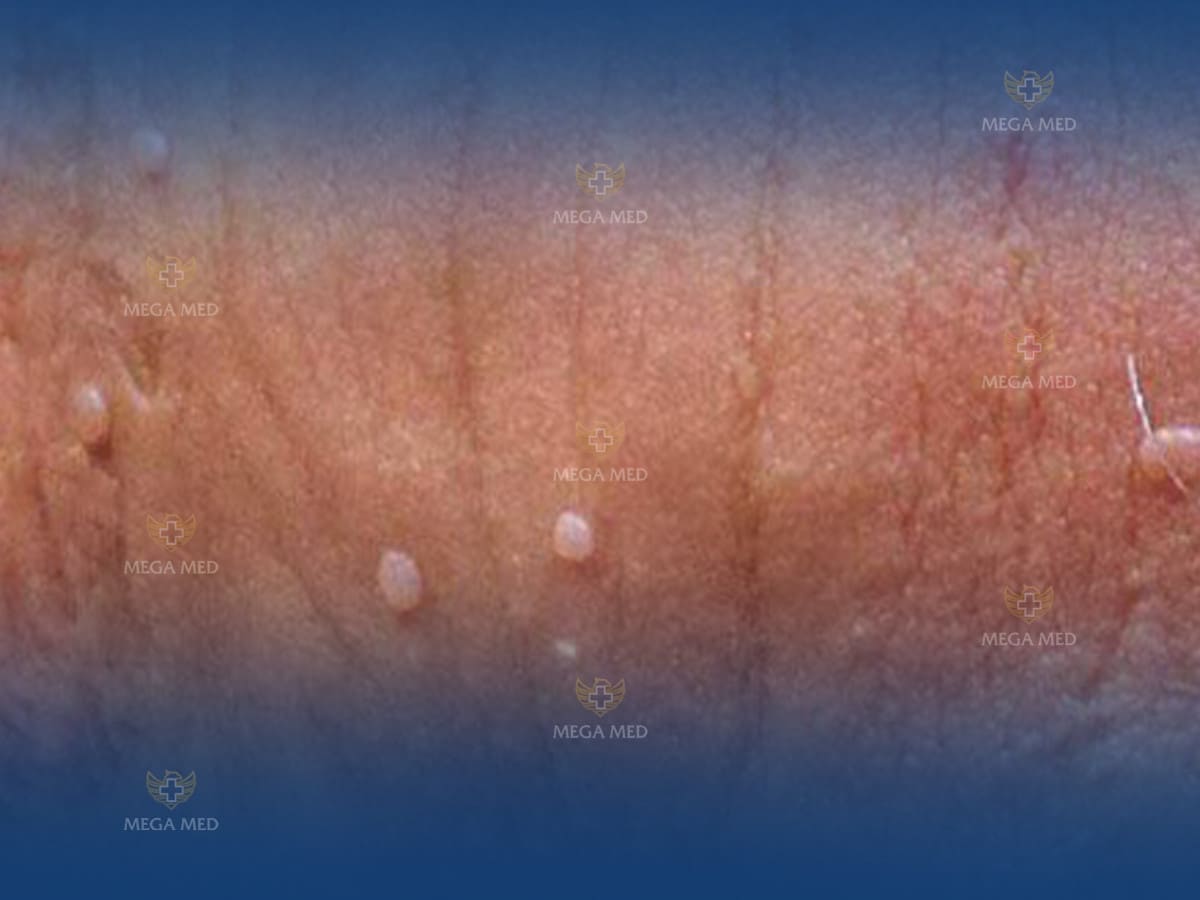

Mặc dù có hơn 200 loại HPV nhưng chỉ có 40 loại có khả năng gây ra sùi mào gà như type 6 và type 11. Mặc dù là một trong những bệnh xã hội phổ biến, nhiều người vẫn đang chậm trễ trong việc phát hiện triệu chứng sùi mào gà vì dễ bị nhầm lẫn với bệnh lý khác như mụn rộp sinh dục hay chuỗi hạt ngọc dương vật.

Ở nam giới, các triệu trứng lâm sàng của sùi mào gà là:

Hình ảnh sùi mào gà trên da nam giới